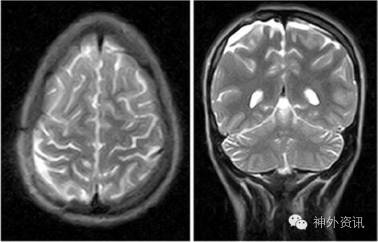

作右额顶部圆形骨窗开颅,切除头颅血肿,并进行颅骨重建手术。患儿术后头痛消失。MRI显示,重建颅骨下方大脑受压缓解(图3)。术后6月复查EEG表明,右侧额顶部异常脑电活动消失(图4)。患儿的学习和注意力轻度障碍也得到改善。

图3. 术后1月MRI-T2像显示,头颅血肿切除,占位效应消失。